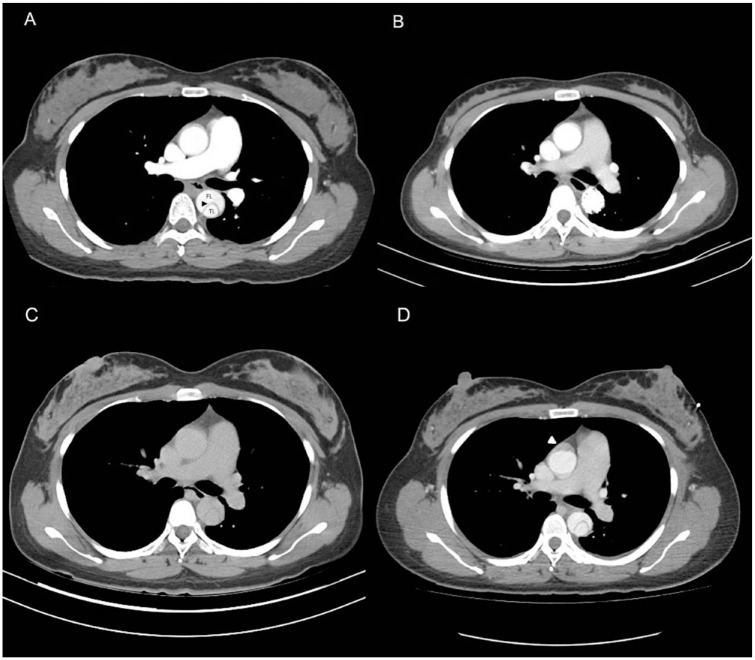

Case report: A case report involving a 33-year-old female with Stanford type B aortic dissection at 32 + 3 weeks gestational age highlights the importance of being alert to the symptoms and signs of this condition, particularly in patients with hypertension or a history of connective tissue disorders. The case report suggests a delivery first strategy followed by TEVAR procedure as the preferred approach for managing aortic dissection in pregnancy. This approach can alleviate pressure on the aorta, reduce the risk of rupture, and provide time for stabilization and preparation for the TEVAR procedure.